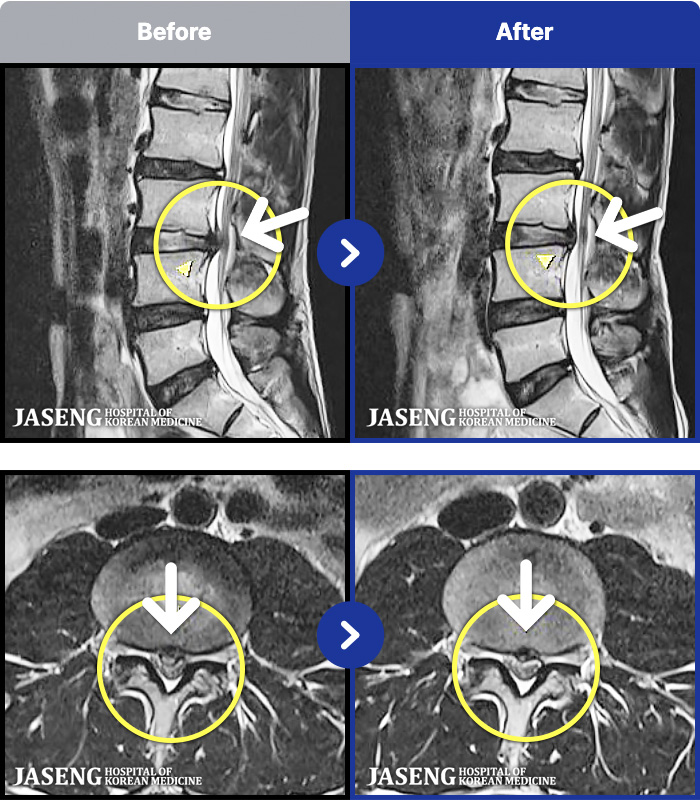

- MRI ġ

MRI ġ

1,299 MRI ũ ʸ Ȯϼ.